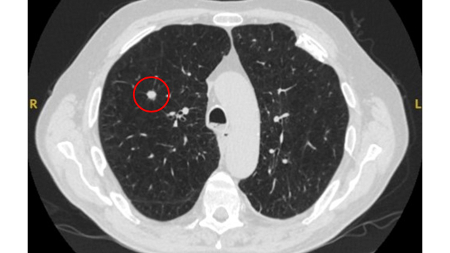

Computed tomography (CT) showing a benign calcified granuloma in the right middle lobe, stable >10 years. The patient reported previous pneumonia on the same side

From the collection of Dr George Tsaknis, MD, PhD, FRCP(London), MRQA, MAcadMEd, PGCert; used with permission